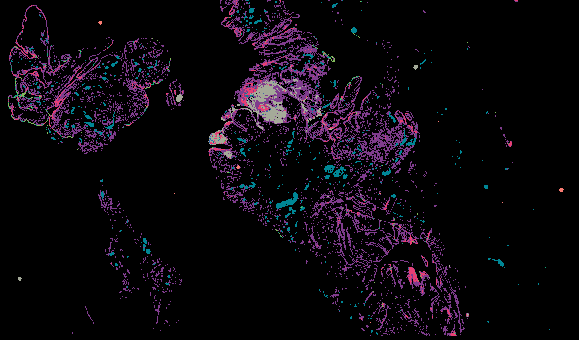

Ovarian Cancer with Annotation - LSP15343